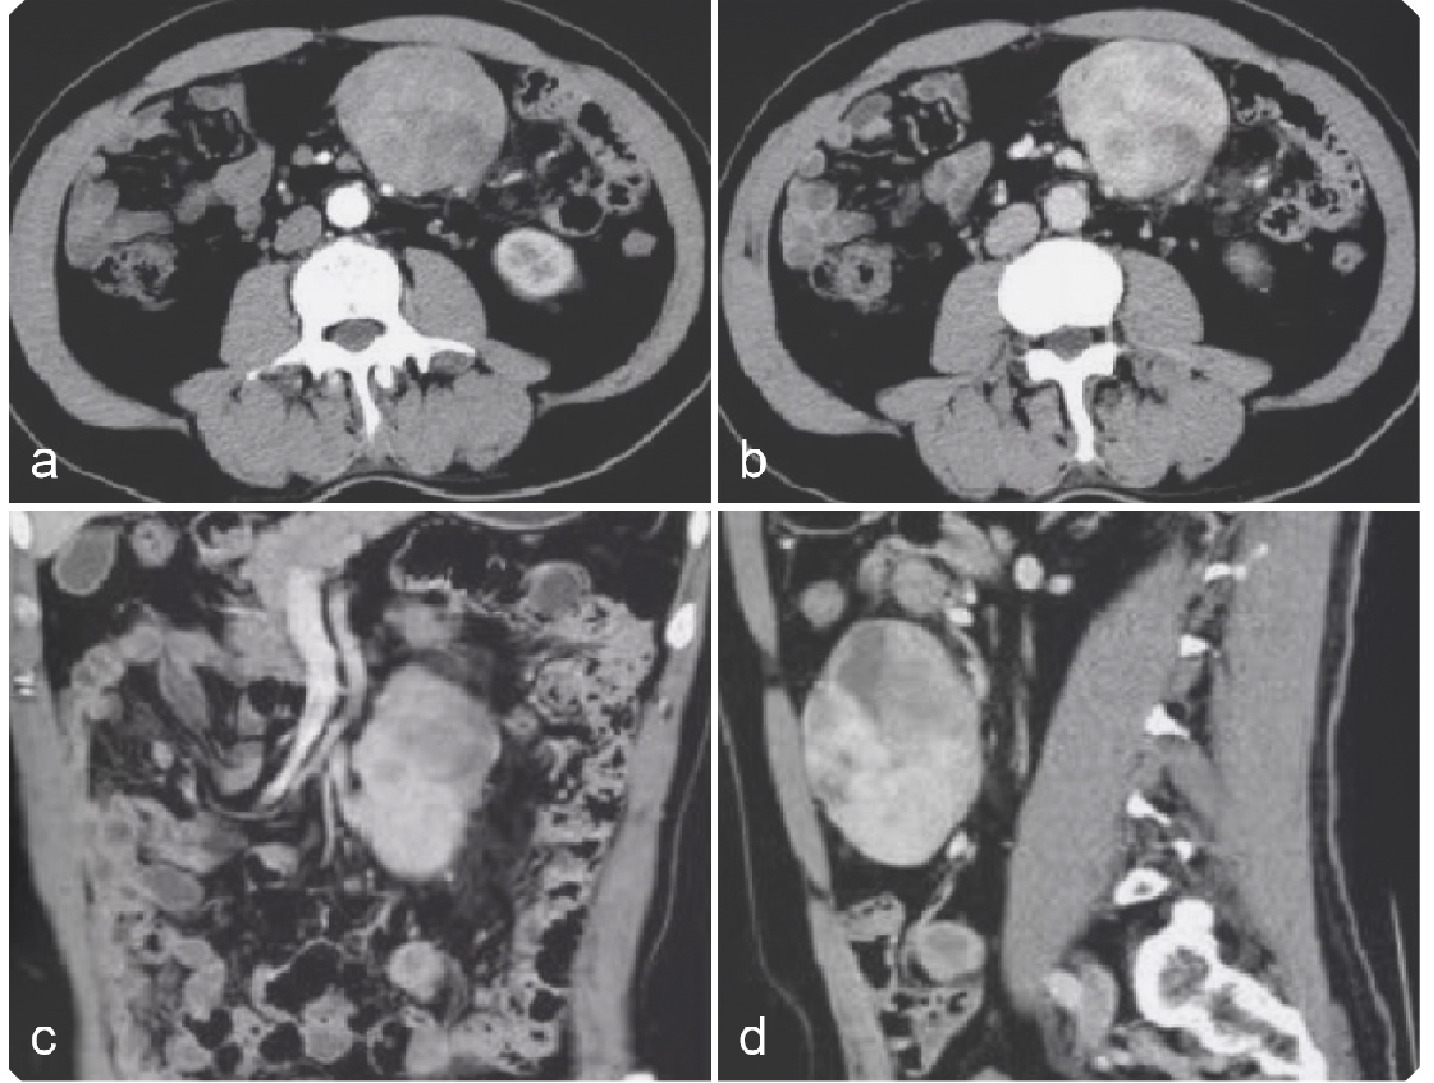

e6b157565c20beba067400577029f65f.png 病例 7:腹膜后(血管外)平滑肉瘤1例

增强CT(横、冠、矢状位)(a、b) 增强扫描动脉期与增强扫描静脉期;(c、d) 冠状位与矢状位影像。腹膜后单发肿瘤,体积较大,边缘规则的软组织肿块,有包膜,内密度不均匀,多发低密度灶;增强扫描,不均匀轻中度强化,内有不强化中心坏死灶与囊变区,门脉期较动脉期强化明显。增强扫描呈轻度渐进性强化,没有明显钙化灶,周围无明显肿大淋巴结。